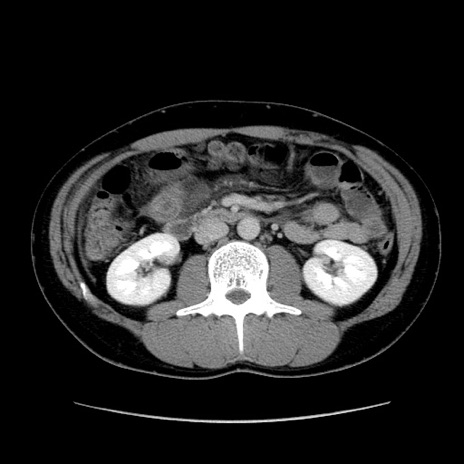

症例36(横断像)

冠状断像

【症例】20歳代 男性

【主訴】心窩部痛

【現病歴】今朝より上腹部痛あり。一旦軽快していたが再度出現したため救急要請。昨日夕に白身の魚を含む刺身を食べた。

【身体所見】BP 136/89mmHg、HR 74/min、BT 37.0℃、腹部:膨満、軟、心窩部に圧痛あり。反跳痛なし、筋性防御なし、腸雑音やや亢進あり。

【データ】WBC 17700、CRP 0.48